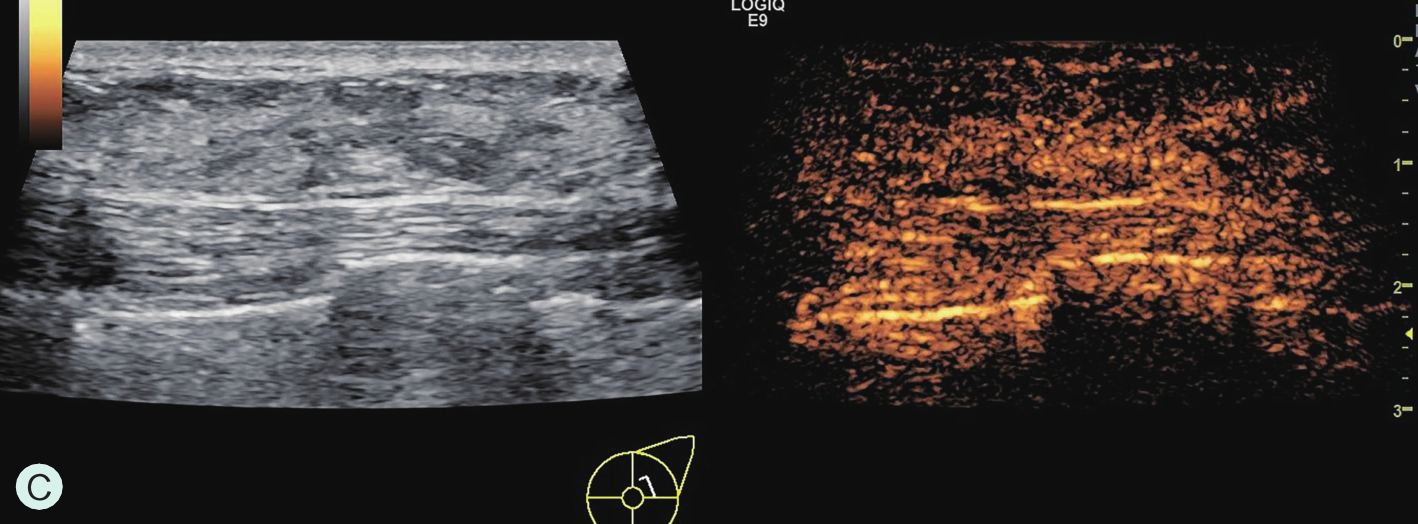

图1-4-3 CEUS时不同乳腺腺体增强强度

A.CEUS背景极少强化;B.CEUS背景轻度强化;C.CEUS背景中度强化;D.CEUS背景重度强化